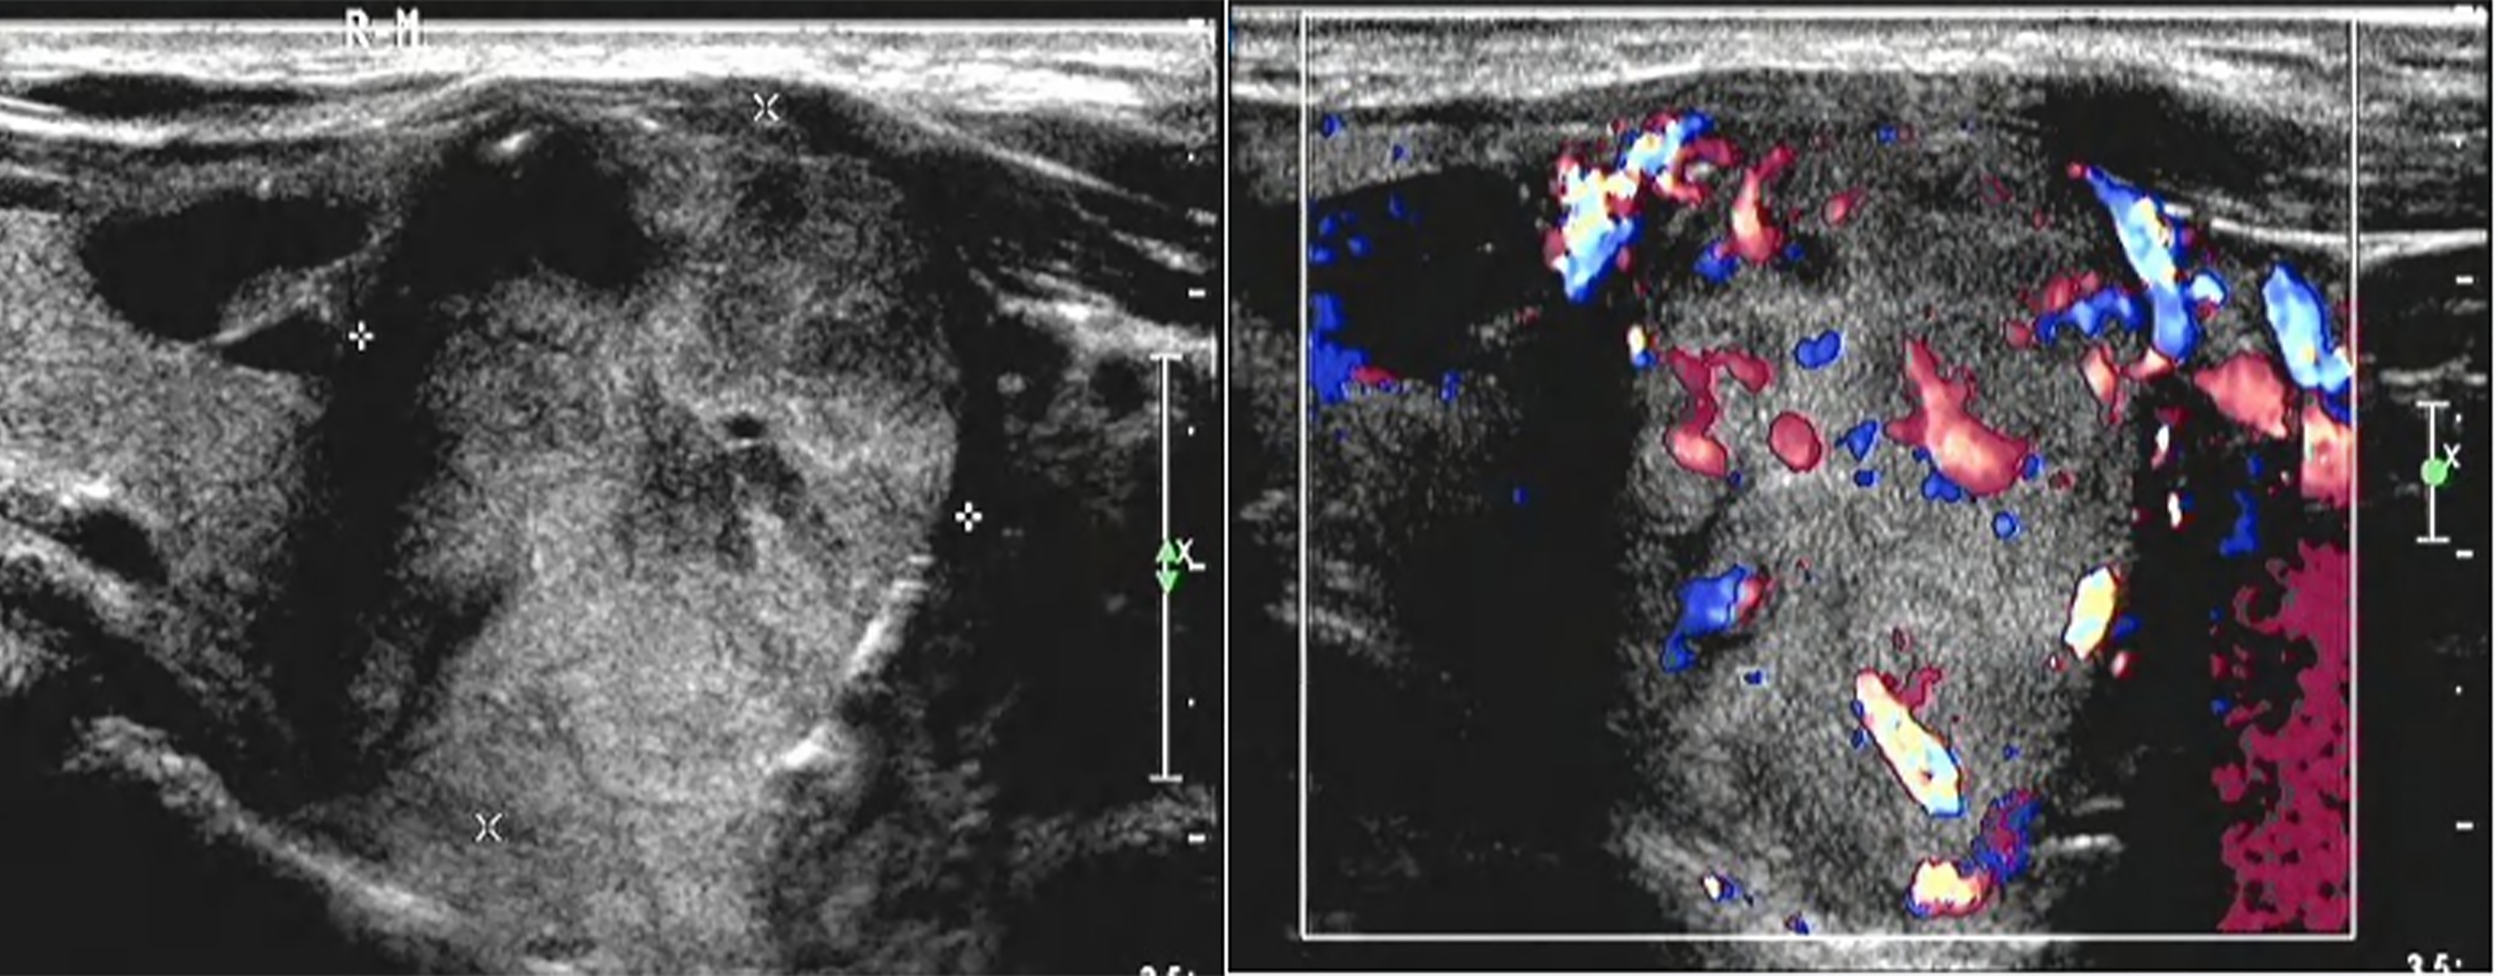

Figure 3

There was a solid lobe nodule on the right side of the thyroid gland, about 30mm × 28mm in size, with clear boundary, mainly solid in the thyroid gland, with irregular and non-echogenic inclusions. A short strip of strong echo could be seen around the nodule, and rich blood flow signals could be seen in and around the nodule.